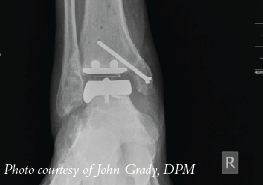

A new study in Foot and Ankle International concludes that among patients having total ankle arthroplasty, outcomes were the same as far as pain and physical performance regardless of age.

The study authors focused on 395 patients who had total ankle arthroplasty with a mean follow-up of 3.5 years. Researchers noted no differences in the Visual Analogue Scale pain score or the physical performance outcomes between the age groups. However, the study did find that patients under age 55 had a greater improvement in Short-Form 36 (SF-36) Vitality and American Orthopaedic Foot & Ankle Society (AOFAS) function scores in comparison with patients over 70.

In his experience performing total ankle arthroplasty procedures, Lawrence DiDomenico, DPM, notes that almost all patients feel a decrease in pain after arthroplasty regardless of age. As he explains, the older patient population fares the best because generally their activity level before and after the surgery is relatively lower in comparison to younger patients.

As a general rule, Dr. DiDomenico suggests using ankle implants in an older population, preferably those who are thin and have a low physical demand, although he notes this is subjective.

“Successful arthroplasty procedures do improve outcomes as the secondary effects on other joints are much better compared with arthrodesis over a long period of time,” says Dr. DiDomenico, the Section Chief of the Department of Podiatry at St. Elizabeth Hospital in Youngstown, Ohio. “(Arthroplasty) also provides a more normal gait compared to arthrodesis, given that the implant is successful.”